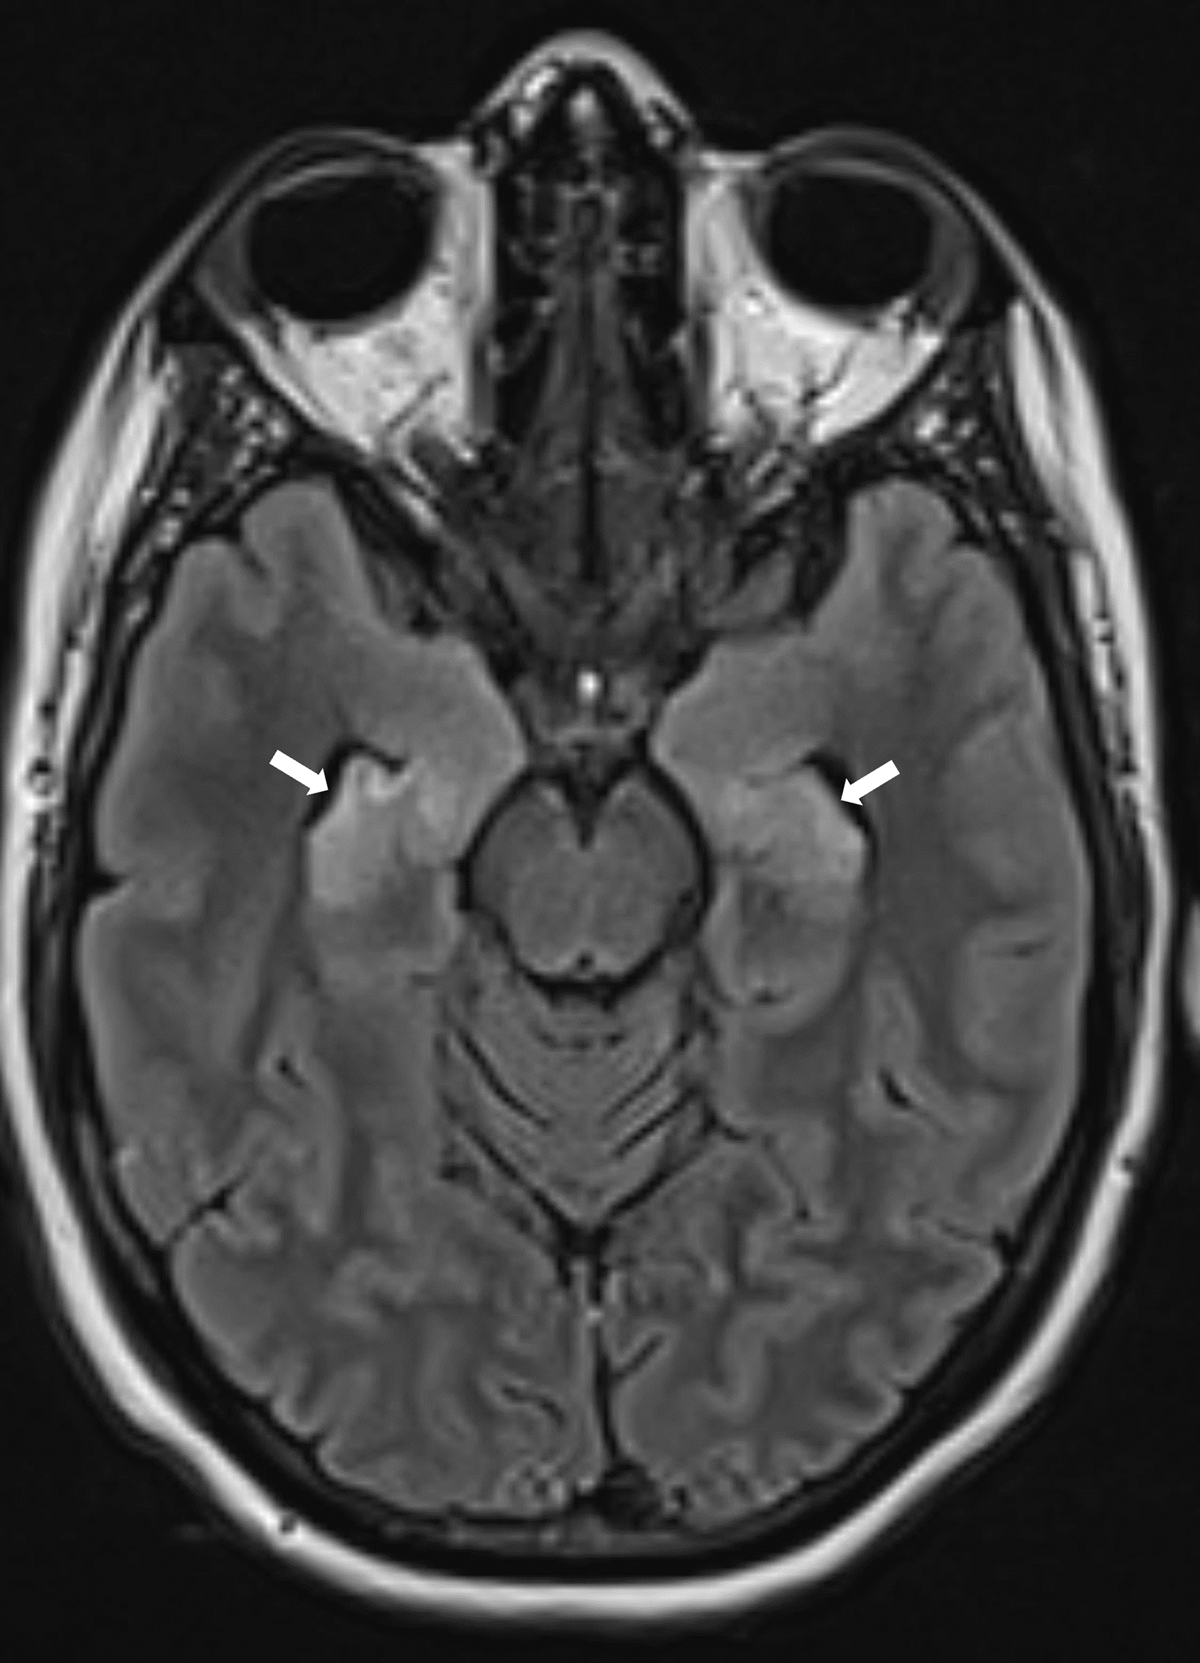

A 39-year-old woman who recently suffered an influenza-infection presented at the ER because of confusion, hallucinations, and progressive neurological decline. During her hospitalisation, she developed focal myoclonic epilepsy which transformed into status epilepticus. Magnetic resonance imaging (MRI) of the brain showed bilateral T2-hyperintense changes in the mesiotemporal structures on axial FLAIR-weighted images (Figure 1, arrows) and on axial and coronal T2-weighted images (Figure 2A–B respectively, arrows). Additionally, a bilateral T2-hyperintense claustrum was seen on axial T2 and axial and coronal FLAIR-weighted images (Figure 3A–C respectively, arrows). Lumbar puncture showed mild pleiocytosis and mildly elevated protein levels. Viral serological and PCR tests were negative. Clinical findings without detection of an acute seizure cause are compatible with febrile infection-related epilepsy syndrome.

Figure 1

The role of imaging is mainly to rule out encephalitis or another structural seizure cause. The majority of (initial) imaging studies in FIRES are normal. When abnormalities are present, these often consist of T2-hyperintense changes in the mesiotemporal regions, with or without signal changes in the basal ganglia or peri-insular region [1]. Evolution to hippocampal sclerosis in the chronic phase is possible.